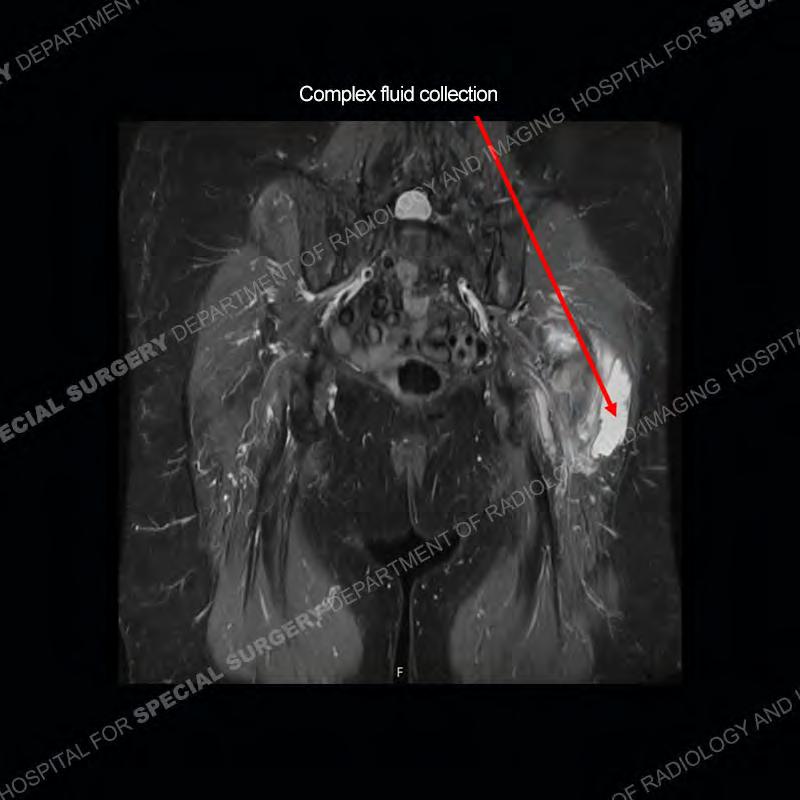

The radiograph is not particularly contributory in this case. The MRI demonstrates markedly abnormal architecture of the gluteus minimus and anterolateral band of the gluteus medius. Portions of the tendons are high signal, portions are highly attenuated, and portions are disrupted. A large, complex fluid collection is present in the adjacent soft tissue.

Diagnosis: Gluteal Tendinosis and Disruption with Complex Trochanteric Bursal Collection